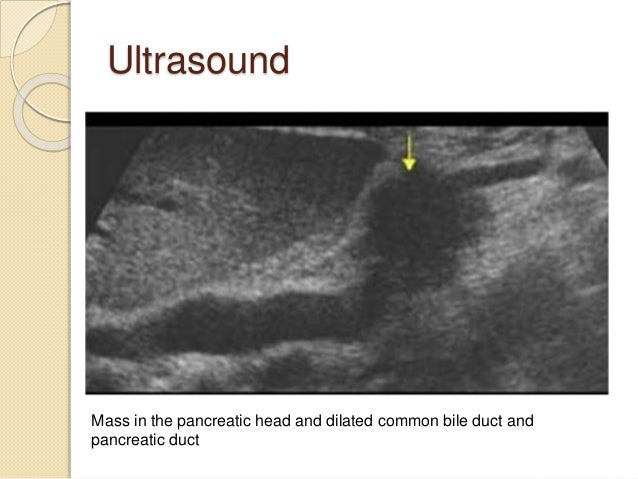

27. 27. Ultrasound study of 900 patients who underwent ultrasound to work up painless jaundice, anorexia, or unexplained weight loss The sensitivity for detection of all tumors in the pancreas was 89 percent Among the 779 patients who were followed over time and established not to have developed a pancreatic tumor, nine had false-positive US findings (specificity 99 percent).

28. 28. Ultrasound Mass in the pancreatic head and dilated common bile duct and pancreatic duct